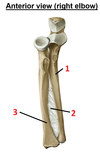

1? 2?

1: Greater tubercule of humerus

2: Coracoid process of scapula